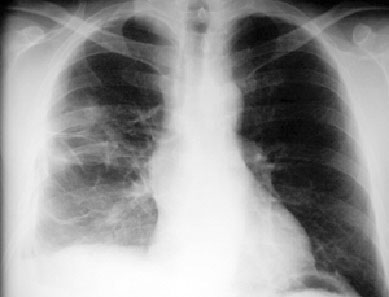

Signo que describe al derrame pleural atrapado en la cisura menor, especialmente en pacientes con insuficiencia cardiaca. El derrame loculado en la proyección posteroanterior se ve como una lesión nodular o masa que simula un tumor sólido (imagen superior). Sin embargo, la evolución rápida hacia la desaparición de esta lesión sugiere que se trata de derrame.

Vemos en las imágenes un tumor fantasma que desaparece en el control realizado cinco días más tarde.